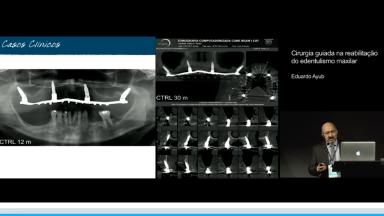

Cirurgia guiada na reabilitação do edentulismo maxilar

Eduardo Antonio Ayub

Esta conferência discute a cirurgia guiada assistida por computador, em maxila totalmente edêntula. As guias cirúrgicas são desenhadas e impressas a partir do planejamento cirúrgico em ambiente virtual, com a utilização de programas de software de planejamento que associam exames de tomografia computadorizada (CT) da anatomia óssea do paciente ao planejamento protético. Apresenta evidências científicas sobre a vantagens clinícas e acuracidade na transferência do posicionamento do implante guiado em comparação com a instalação de implantes a mão livre. Concluindo que, por meio da sistematização do planejamento, junto a procedimentos cirúrgicos guiados, é possível otimizar a cirurgia, minimizar complicações e oferecer mais conforto para o paciente.